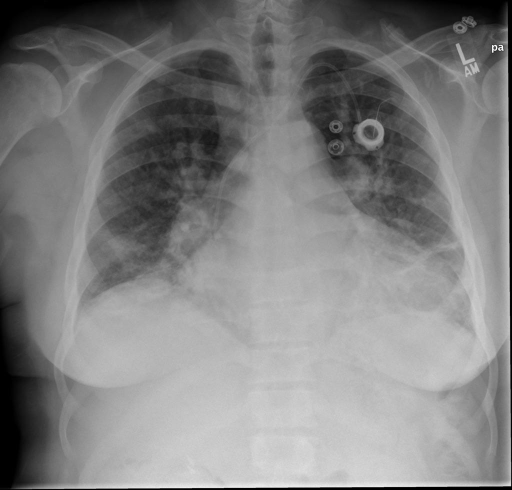

Comparison of CXAS to Human Anatomy Annotations on Real World Chest X-Rays

To test the real-world applicability of PAX-Ray++ for developing anatomy segmentation models, we prepare a test set of 30 frontal and lateral chest X-Rays each from the PadChest dataset [38] for a total fo 60 images. First, we use our best segmentation model based on the validation performance to generate preliminary anatomical segmentations. Then, we tasked two medical experts to independently examine and correct these densely annotated X-Rays using the annotation tool CVAT [39]. Even in this simplified annotation process, the expert denoted that a single image correction would take roughly 1.5 hours on average due to the sheer amount of considered classes.

We display qualitative results in Fig. 3. The annotators tend to be content with most annotations. There are edits at the extensions of the esophagus, trachea, and aorta and corrections of the lower ribs. There is little consensus for classes in the abdominal area, such as the stomach, as seen on the right of Fig. 3 . In contrast, the annotators often align for bone classes.

We show the quantitative segmentation performance against medical expert annotations for all classes in Fig. 3 . The dashed lines represent the IAA, whereas the dotted line displays the average MAA. As the task for the human annotators was not to annotate from scratch but to correct wrong pixel-wise predictions, we can see a high MAA for most classes. In the frontal view, the most significant disagreements exist for rare bone structures such as L3 and C4, lower ribs, the mediastinal distribution, or the breast tissue. The IAA and MAA are highly similar with mIoU of respective 95% and 94%. The Hausdorff distance for MAA is slightly lower than the IAA, indicating slight differences in boundary annotations while maintaining a considerable overlap with the other annotator. In the lateral view, the concrete delineation of rib structures appears ambiguous, leading to lower MAA and IAA with a greater IAA than MAA for all metrics in this supercategory. Overall there is less agreement between the medical experts in the lateral view, leading to a better average MAA than IAA across all metrics (i.e. 85% vs 83% mIoU). While the experts propose changes to the original predictions, they are often not overlapping. In the lateral view, rib segmentations can become quite hard to interpret. While both annotators disagree with the rib segmentations, they do not always agree on how they should look. Similarly to the frontal view, tube-like structures like the esophagus are extended as they can appear fractured at times.